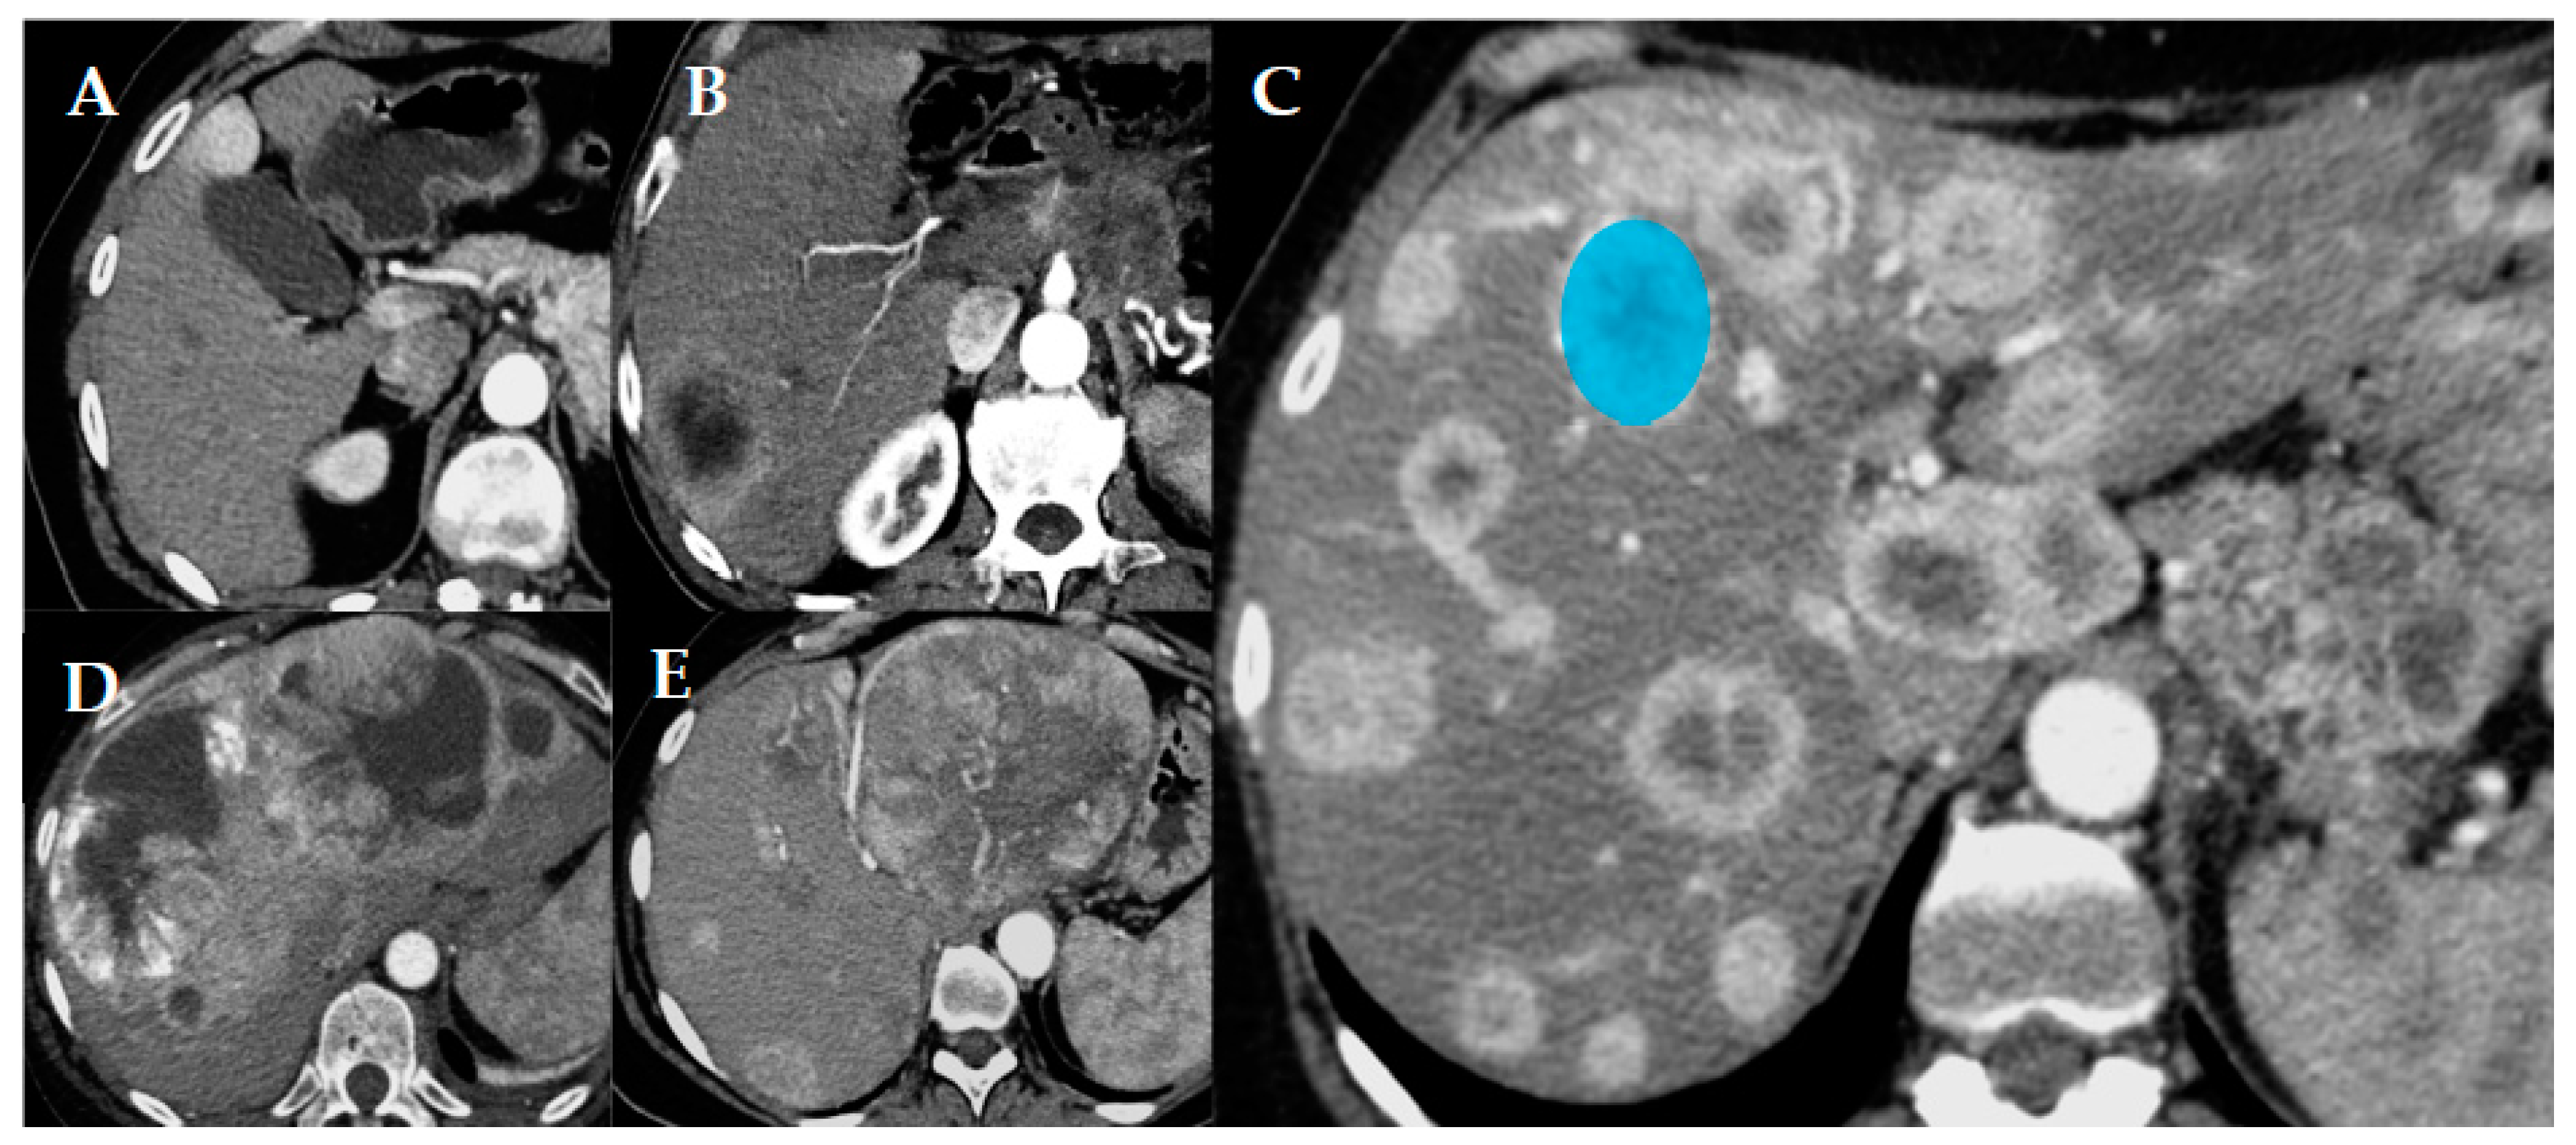

2.2. Imaging Technique and Evaluation

CT scans acquired in our institute were performed with a multi-slice equipment before and after 1.5 mL/kg intravenous injection of iodine contrast media during arterial phase (15 s after aortic peak) and/or venous phase (60–70 s). Section thickness was 2 mm. The quantitative parameters evaluated were: number of metastases, volume, and major diameter of the largest metastases. Qualitative parameters evaluated were: relative density of metastases in precontrastographic phase, relative enhancement after administration of contrast medium during arterial and venous phase, and pattern of metastatic spread. This pattern (Figure 1) was categorized as follows: uninodular (one lesion), paucinodular (from two to six metastases), multinodular without coalescence of metastases (over six metastases, which remain separated), confluent multinodular, and bulky (huge lesions involving a great portion of the liver, independent of the number of metastases). Unilobar or bilobar involvement of the liver was always evaluated [6]. Other qualitative parameters evaluated were: margins of metastases (sharp or infiltrating), and presence of calcifications, necrosis, and a cystic component. When CT imaging was incomplete or unavailable, the available MR images were consulted for the evaluation of the only missing quantitative (number and dimensions of metastases) and qualitative (relative enhancement and pattern of metastases) characteristics.

2.3. Texture Analysis

Texture analysis was performed on the larger vital area of the most representative metastasis, in a single slice, in the arterial (Art) and/or venous (Ven) phase of the CT. The choice of the most representative metastasis on which to place the volume of interest (VOI) for texture analysis (Figure 1) was made arbitrarily according to the following priority criteria in order: absence of artifacts within the lesion; absence of macroscopic cystic components, large areas of necrosis, or coarse calcifications; and a larger lesion available in accordance with previous criteria. Both first- and second-order texture parameters were tested, but only first-order parameters were finally used for the analyses. In particular, the following histogram-derived parameters were included: mean Hounsfield Unit (HU) value, skewness, kurtosis, entropy, and uniformity. Skewness describes the asymmetry of the grey-level distribution in the histogram. Kurtosis reflects the shape of the grey-level distribution (peaked or flat) relative to a normal distribution. Entropy, expressed as log2, reflects the randomness of the distribution, while uniformity reflects the uniformity of the distribution. Texture analysis was performed using LIFEx v5.10 software [24] for Mac OS on all the CT exams for which the complete DICOM file was retrievable.

Figure 1. Different patterns of pancreatic neuroendocrine tumor (p-NET) metastatic spread in the liver. Uninodular (A), paucinodular (B), multinodular (C), confluent multinodular (D), and bulky (E). In image (C) an example of how the volume of interest (VOI; blue circle) was placed when performing the texture analysis is reported.